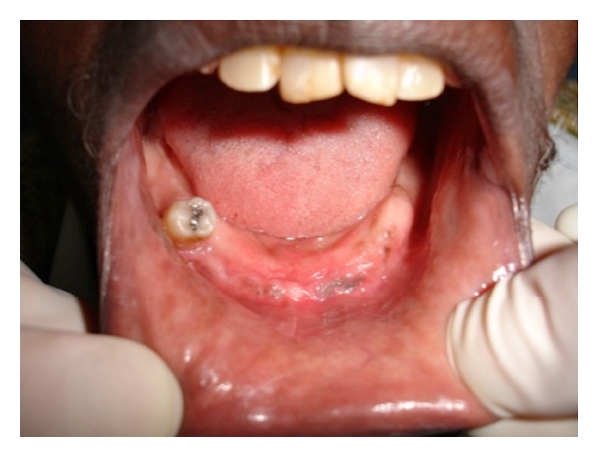

Case 1. A 77-year-old white female was seen at the Oral Medicine Clinic of the Federal University of Alfenas (UNIFAL-MG) with an asymptomatic, smooth surfaced, normal colored tumor on the anterior mandibular alveolar ridge, with two months evolution. A drainage point with purulent material was also present (Figure 1(a)). The patient’s medical history was unremarkable and no changes were noted on extraoral examination. Radiographic examination revealed osteolysis and bone sequestration on the mandibular alveolar ridge (Figure 1(b)). Based on clinical and radiographic findings, a provisional diagnosis of osteomyelitis was rendered. The patient was given amoxicillin (500 mg, three times/day) for 15 days and subsequently underwent excision of the bone sequestrum and curettage of the granulation tissue (Figure 2). The material was submitted to histopathological examination which revealed nonviable bone and a mixed inflammatory infiltrate of lymphocytes and plasma cells, confirming the diagnosis of chronic suppurative osteomyelitis. The area healed appropriately within one month (Figures 3(a) and 3(b)). The patient has been under follow-up for 5 years with no signs of recurrence.

(a)

(b)